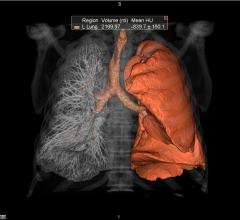

Vital Images Inc. recently announced the support of Nuance PowerScribe 360 Reporting and PenRad PenLung Lung Screening Management system in its comprehensive Lung Screening solution. The Vitrea CT Lung Analysis application helps clinicians standardize the diagnosis of lung nodules, while the solution’s workflow system facilitates management of lung screening treatment plans.